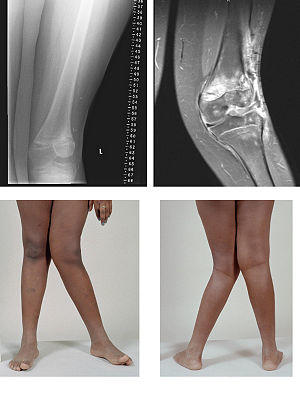

Valgus Deformity MRI and photograph

A valgus deformity is a condition in which the bone segment distal to a joint is angled outward, that is, angled laterally, away from the body's midline.[1] The opposite deformation, where the twist or angulation is directed medially, toward the center of the body, is called varus. Common causes of valgus knee (genu valgum or "knock-knee") in adults include arthritis of the knee and traumatic injuries.

Rheumatoid knee commonly presents as valgus knee. Osteoarthritis knee may also sometimes present with valgus deformity though varus deformity is common. Total knee arthroplasty (TKA) to correct valgus deformity is surgically difficult and requires specialized implants called constrained condylar knees.